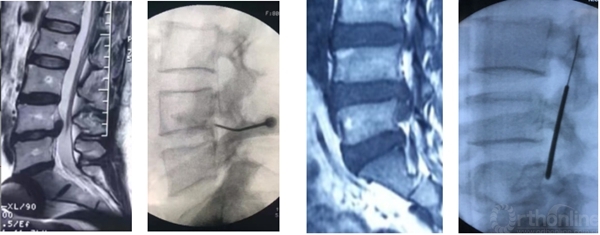

有些病例椎板间入路手术更加简单,尤其对于L5/S1脱垂病例

高度脱垂病例可选择椎板开窗入路,需准备磨钻动力系统

L5/S1钙化型突出(骺环离断症),椎板间减压更加充分彻底,需配备磨钻动力系统

术前造影显示后纵韧带完整性,术中保护后纵韧带

脊柱内镜日间手术需进一步提高穿刺的精准性,避免反复穿刺。

靶向穿刺